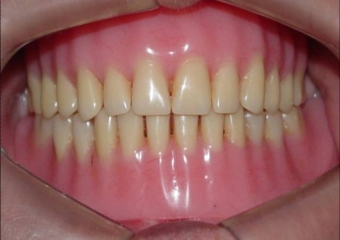

Prótese fixa sobre implantes inferior e nova prótese superior

Sorriso final do caso terminado em abril de 2012